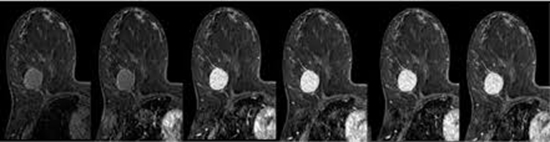

ارزش تشخیصی کنتراست پویا مغناطیسی تقویت شده (DCE/MRI) پرفیوژن در پیش بینی پاسخ به شیمی درمانی Neoadjuvant در سرطان پستان

کنتراست تقویت شده (DCE-MRI) پرفیوژن در پاسخ به شیمی درمانی Neoadjuvant در سرطان پستان